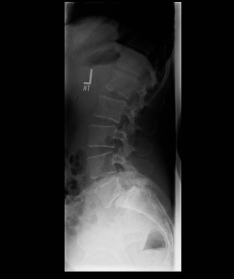

Spondylolisthese

Spondylolisthesis refers to a slipped vertebra, i.e. a displacement of the upper vertebra with respect to the lower one. This can occur degeneratively due to joint wear or due to a disruption of the vertebral arch, which is usually a consequence of an unnoticed and unhealed fracture. A slipped vertebra often becomes symptomatic through an instability-related pain on exertion (getting up from a chair is only possible with the help of the arms). However, it is not uncommon for the vertebral displacement to lead to secondary spinal canal stenosis, which then becomes noticeable as pain extending into the legs.

X-ray image of a slipped vertebra in the lower lumbar spine before and after surgery